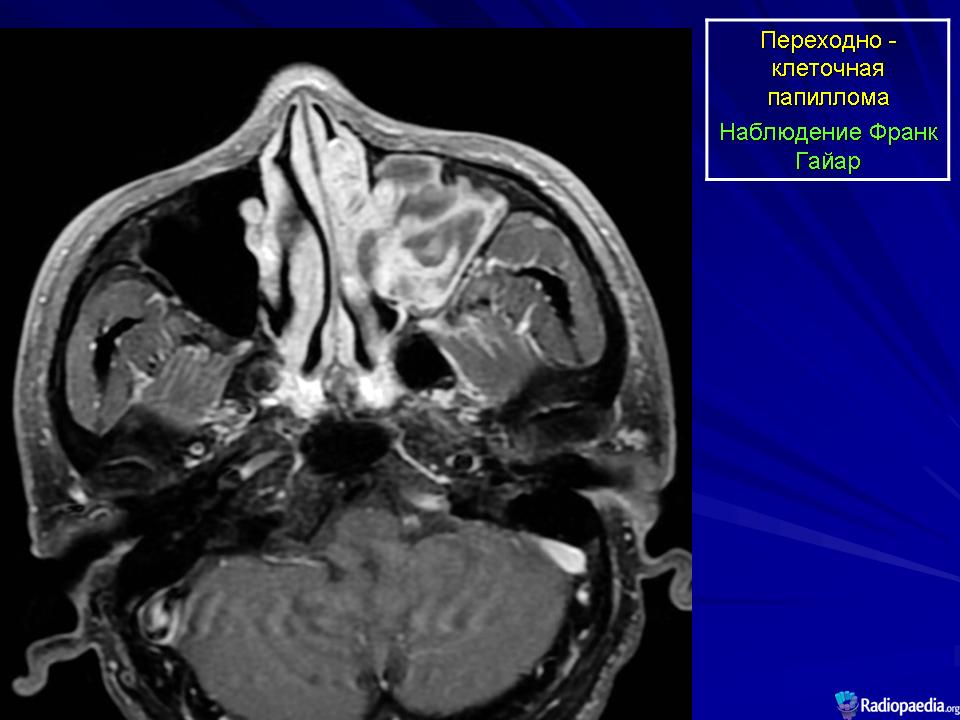

Переходно-клеточная папиллома.

Инвертированная переходно-клеточная папиллома (син.: папиллома Шнейдера, эпителиальная папиллома, сосочковая фиброэпителиома, папиллярный синусит, цилиндроклеточная папиллома, папиллома из респираторного эпителия) — редкая, но характерная для полости носа и его синусов доброкачественная опухоль, составляющая около 0,5 % от находок всех новообразований носа. Она чаще встречается у мужчин, преимущественно на пятом-шестом десятилетии жизни. Обычно односторонняя, эта опухоль бывает одиночной и множественной. Как правило, она возникает на боковой стенке полости носа, а также в околоносовых пазухах: гайморовой полости, решетчатом лабиринте, изредка в лобной и основной пазухах. При сочетанном поражении локализацию первичного узла установить практически невозможно. Из полости носа опухоль может врастать в околоносовую пазуху и наоборот. Пациенты обычно жалуются на заложенность носа, выделения, носовые кровотечения, боль в области лицевого нерва. Иногда в зоне опухолевого роста происходит разрушение костной ткани. Чаше всего страдают стенки гайморовой пазухи. Но опухоль может расти и в других направлениях, разрушая стенку неба, стенки глазницы или кости основания черепа. Рецидивы опухоли могут возникать через 5—10 лет. Примерно у 5% больных инвертированная переходно-клеточная папиллома способна превращаться в рак после долголетнего доброкачественного течения. Метастазы не наблюдаются.

Макроскопически мягкая, со складками, опухоль имеет дольчатое, сосочковое строение, шероховатую поверхность. Цвет ее ткани варьирует от розового до желто-красного. Инвертированная переходно-клеточная папиллома рецидивирует в 75 % случаев, если проведена локальная эксцизия. Для оптимального лечения при локализации опухоли на боковой стенке носовой полости рекомендуется боковая ринотомия и срединная резекция верхней челюсти. Если такая папиллома малигнизируется, то ее клиническое течение становится более агрессивным.